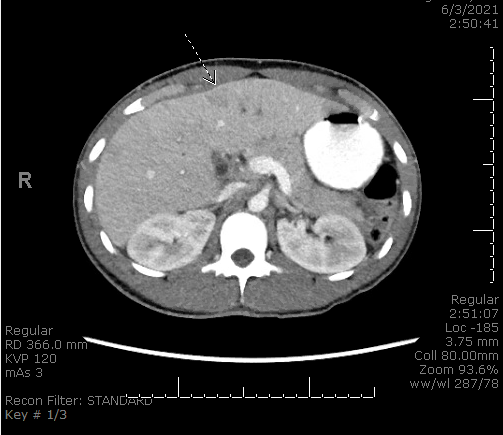

Case Presentation: A 24-year-old male with a history of acute pancreatitis three months prior, presented with sharp peri-umbilical and right upper quadrant abdominal pain for three weeks. He endorsed fevers, rigors, jaundice, nausea, vomiting, poor appetite, and dark colored urine. He denied hematemesis, melena or hematochezia. He had intermittent alcohol use but no illicit drug or tobacco use. On arrival, he was septic with tenderness on abdominal palpation. He had a leukocytosis, hyperbilirubinemia, transaminitis, elevated alkaline phosphatase and lipase levels. Imaging demonstrated intrahepatic biliary dilation, gallbladder inflammation, concern for choledocholithiasis with obstructing stone, and colonic wall thickening at the hepatic flexure. There was also bilobar portal venous thrombophlebitis with areas of hypoattenuation. He was started on broad-spectrum antibiotics and resuscitated with fluids. An urgent ERCP demonstrated no pus or obstruction, but he required biliary sphincterotomy with sludge clearance, percutaneous cholecystostomy drain placement and ventral pancreatic duct stenting. He was started on a heparin drip. A hypercoagulable workup was unremarkable. Four days post-procedure, he developed worsening hyperbilirubinemia and large melanotic stools. Repeat ERCP demonstrated bleeding at the sphincterotomy that was treated. He was resumed on heparin and transitioned to apixaban when bleeding resolved. The patient also had a polymicrobial bacteremia and discharged on oral Levaquin and Flagyl. His liver function improved and anticoagulation was stopped at three months later.